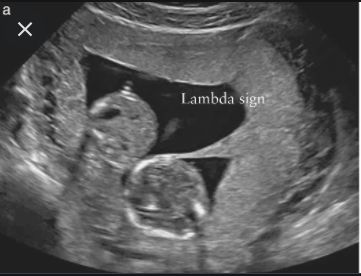

"Lambda/Twin-peak sign" is the sonographic image seen in a _____chorionic twin pregnancy.

The following is a _____chorionic _____amniotic placenta

Flashcard 6: "Lambda/Twin-peak sign" is the sonographic image seen in a _____chorionic twin pregnancy.

Answer: di

Flashcard 7: The following is a _____chorionic _____amniotic placenta

Answer: mono